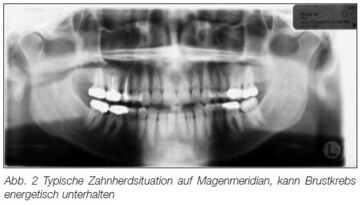

| − | [[image:Rau2.jpg|Bild aus einem Artikel von [[Thomas Rau]] bei [[Sanum-Therapie|"Sanum-Post"]] mit Bezug zur [[Meridian]]-Lehre aus der TCM<ref>http://www.sanum.com/pdf/86_rau_mammacarcinom.pdf</ref>| | + | [[image:Rau2.jpg|Bild aus einem Artikel von [[Thomas Rau]] bei [[Sanum-Therapie|"Sanum-Post"]] mit Bezug zur [[Meridian]]-Lehre aus der TCM<ref>http://www.sanum.com/pdf/86_rau_mammacarcinom.pdf</ref>|360px|thumb]] |